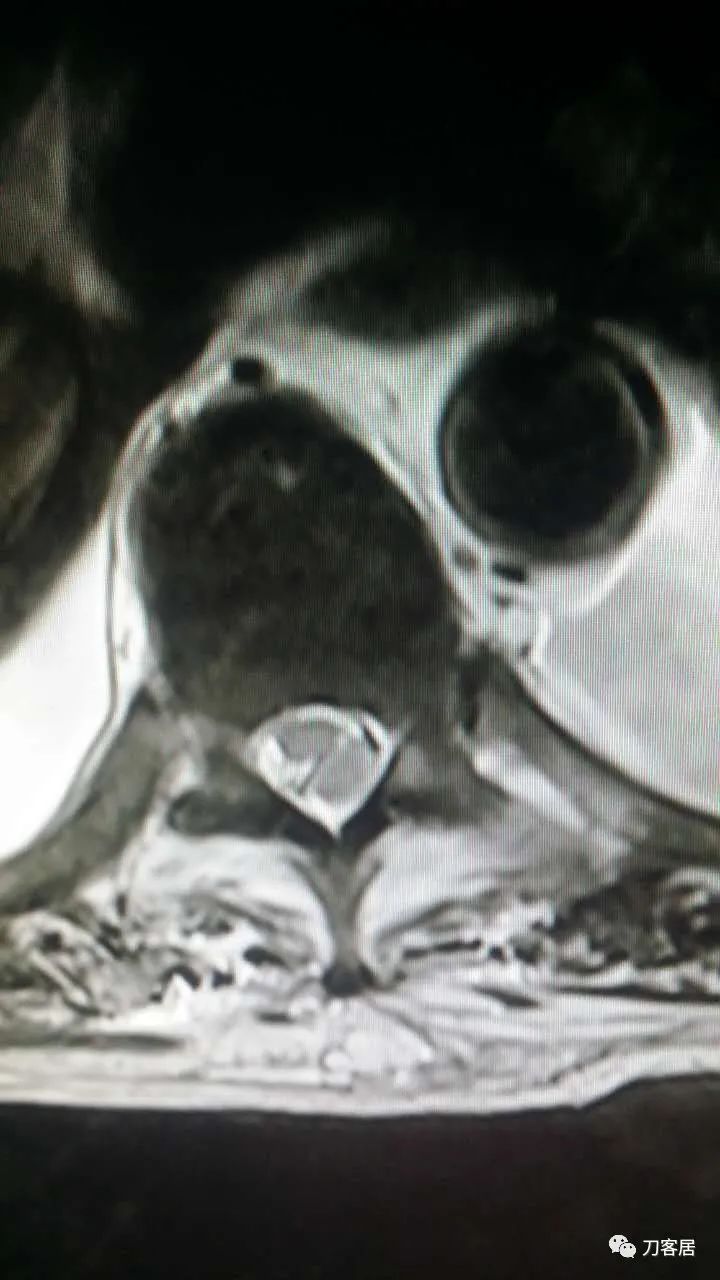

加注图10: 腰1-2椎管内后方可见梭形占位信号改变。

加注图11. 腰1-2椎管内后方可见梭形占位信号改变。